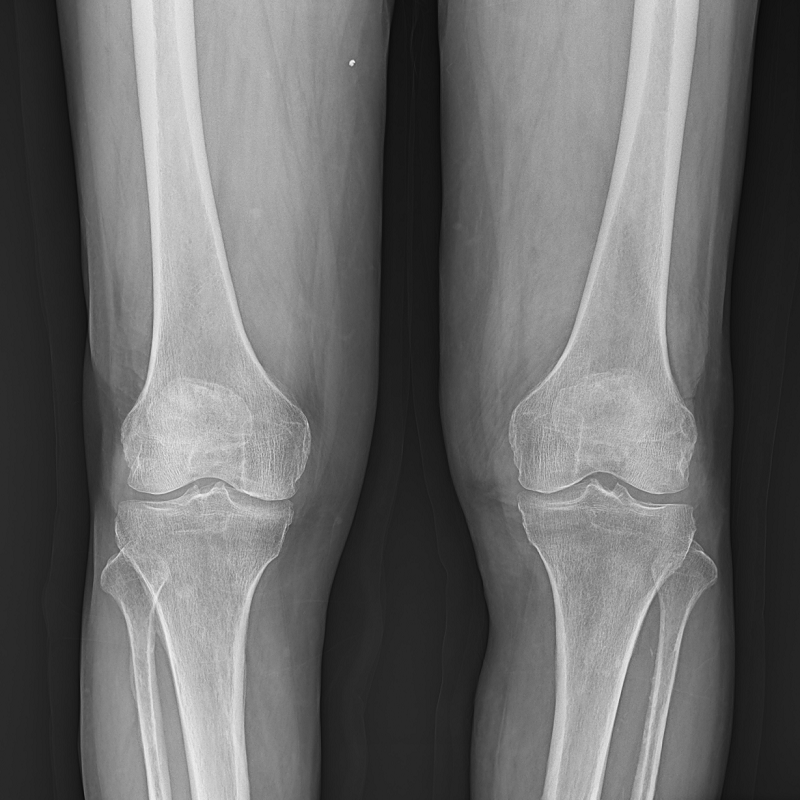

●呈現(xiàn)全下肢或全脊柱圖像

●在脊柱及下肢畸形矯正手術(shù)治療中,為術(shù)前方案制定和術(shù)后復(fù)查提供精準(zhǔn)測量

●有效解決傳統(tǒng)X光片不能一次成像問題,為患者提供更加優(yōu)質(zhì)的醫(yī)療服務(wù)

點(diǎn)片裝置可實(shí)現(xiàn)大范圍縱向移動,高效完成各部位、全身拼接等檢查需求